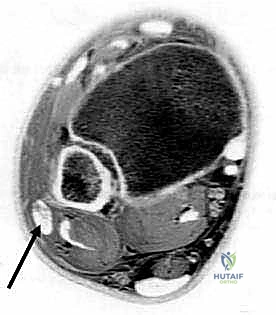

- الموجات فوق الصوتية الحركية (Dynamic Ultrasound): تقنية ممتازة تتيح للدكتور رؤية الوتر وهو ينزلق خارج مكانه أثناء حركة المريض المباشرة.

- الرنين المغناطيسي (MRI): هو المعيار الذهبي. يوضح بدقة متناهية شكل الميزاب العظمي، حالة القيد الليفي (SPR)، وما إذا كان هناك تمزق طولي مصاحب في الأوتار نفسها.